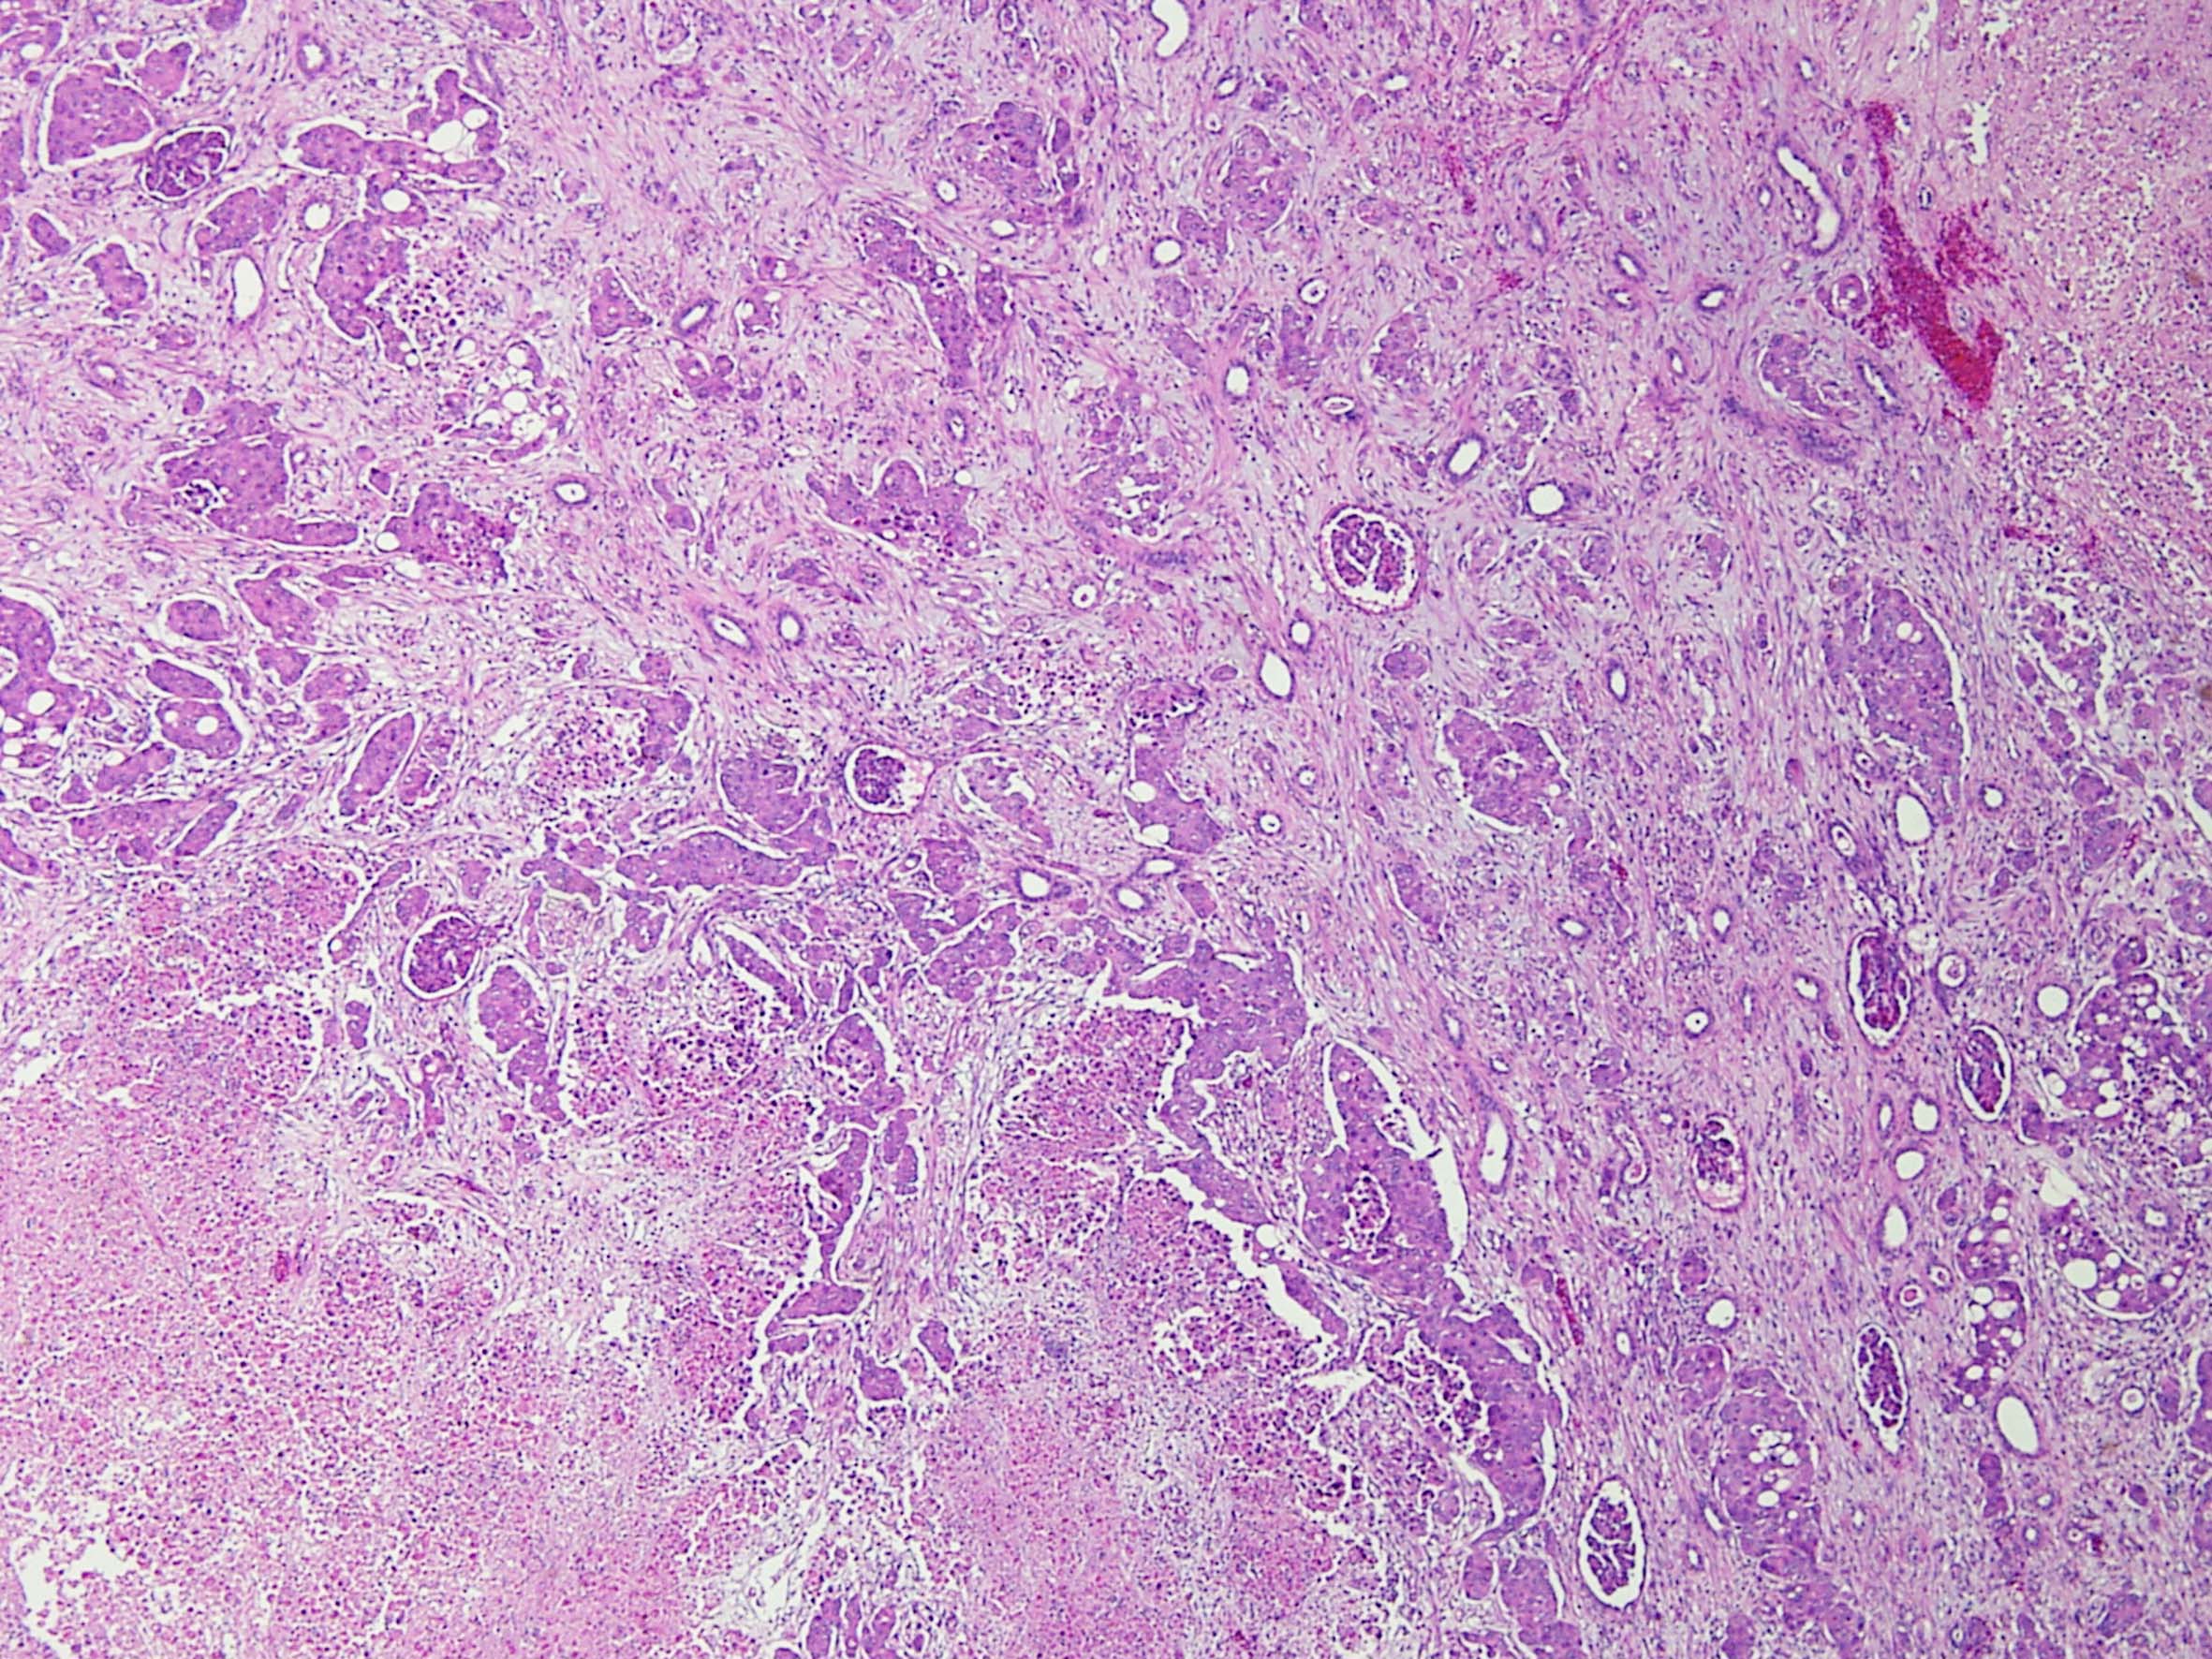

Consensus grade: Renal Medullary carcinoma

Case description (by case creator):

Renal medullary carcinoma